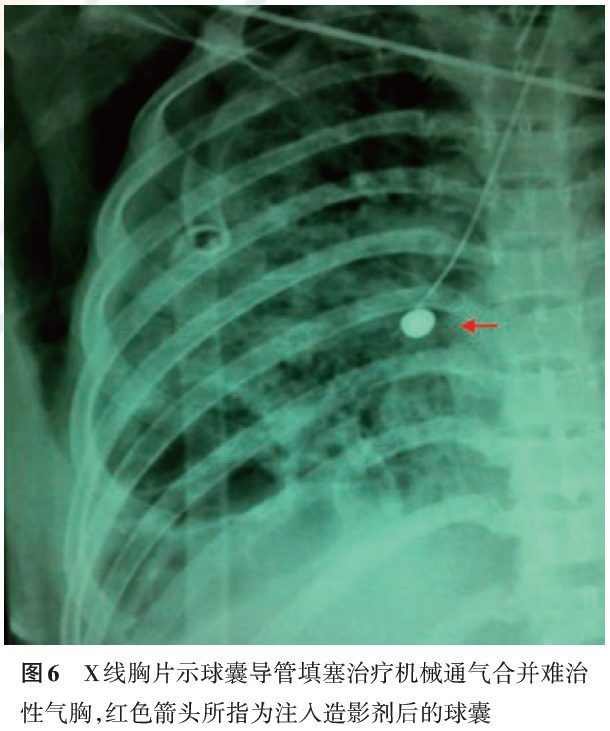

1)材料:球囊导管填塞主要用于机械通气并发难治性气胸,可起到保证有效通气量及促进破裂口愈合的作用。机械通气合并气胸在急性呼吸衰竭中提示预后不良,其病死率为50%~67%,机械通气合并难治性气胸使用封堵剂对责任引流支气管进行封堵不太恰当,这主要是由于封堵剂很难立刻被取出或清除,如果发生因封堵剂堵塞肺组织而导致通气及换气功能恶化则无法使被封堵的肺叶肺段马上恢复通气。而使用球囊导管填塞漏气支气管则法符合随时撤消封堵的要求,放置过程亦无需中断机械通气,这对于存在心肺功能不全的老年患者尤为重要(图6)。

2)技术流程:①确定目标支气管:送入支气管镜,如患者正在进行机械通气,则可将气管导管球囊适量放气以便支气管镜从球囊边通过。探查方法按前述步骤进行;②放置导丝:确定目标支气管后,退出球囊导管,经支气管镜工作通道将导丝送入目标支气管,接着退出支气管镜;③沿导丝将球囊导管送入目标支气管,并再次进镜确保球囊位置正确,向球囊中注入水溶性碘造影剂充盈球囊(可在X线下显影)使之填塞目标支气管,观察引流瓶中气体引流情况;④注意事项:球囊导管填塞成功后可行床旁X线胸片,确定球囊位置以备治疗过程中复查时对照。当球囊导管填塞目标支气管后应当继续留下置导丝,并使导丝从导管先端部向目标支气管远端伸出3~4 cm,以防止在咳嗽时球囊导管被弹出移位。

3)疗效及并发症:1982年Ellis等报道了1例采用球囊导管填塞治疗机械通气并发难治性气胸取得成功的病例。机械通气并发气胸使有效通气量的维持变得困难、使通气/血流变得进一步失调,这是一种高危状态。而Ellis的经验为这一棘手的难题提供了一种值得尝试的解决途径。当然近年来随着肺减容活瓣及支气管塞在难治性气胸的成功应用,采用这两种封堵器治疗机械通气并发气胸应该可行且有效。